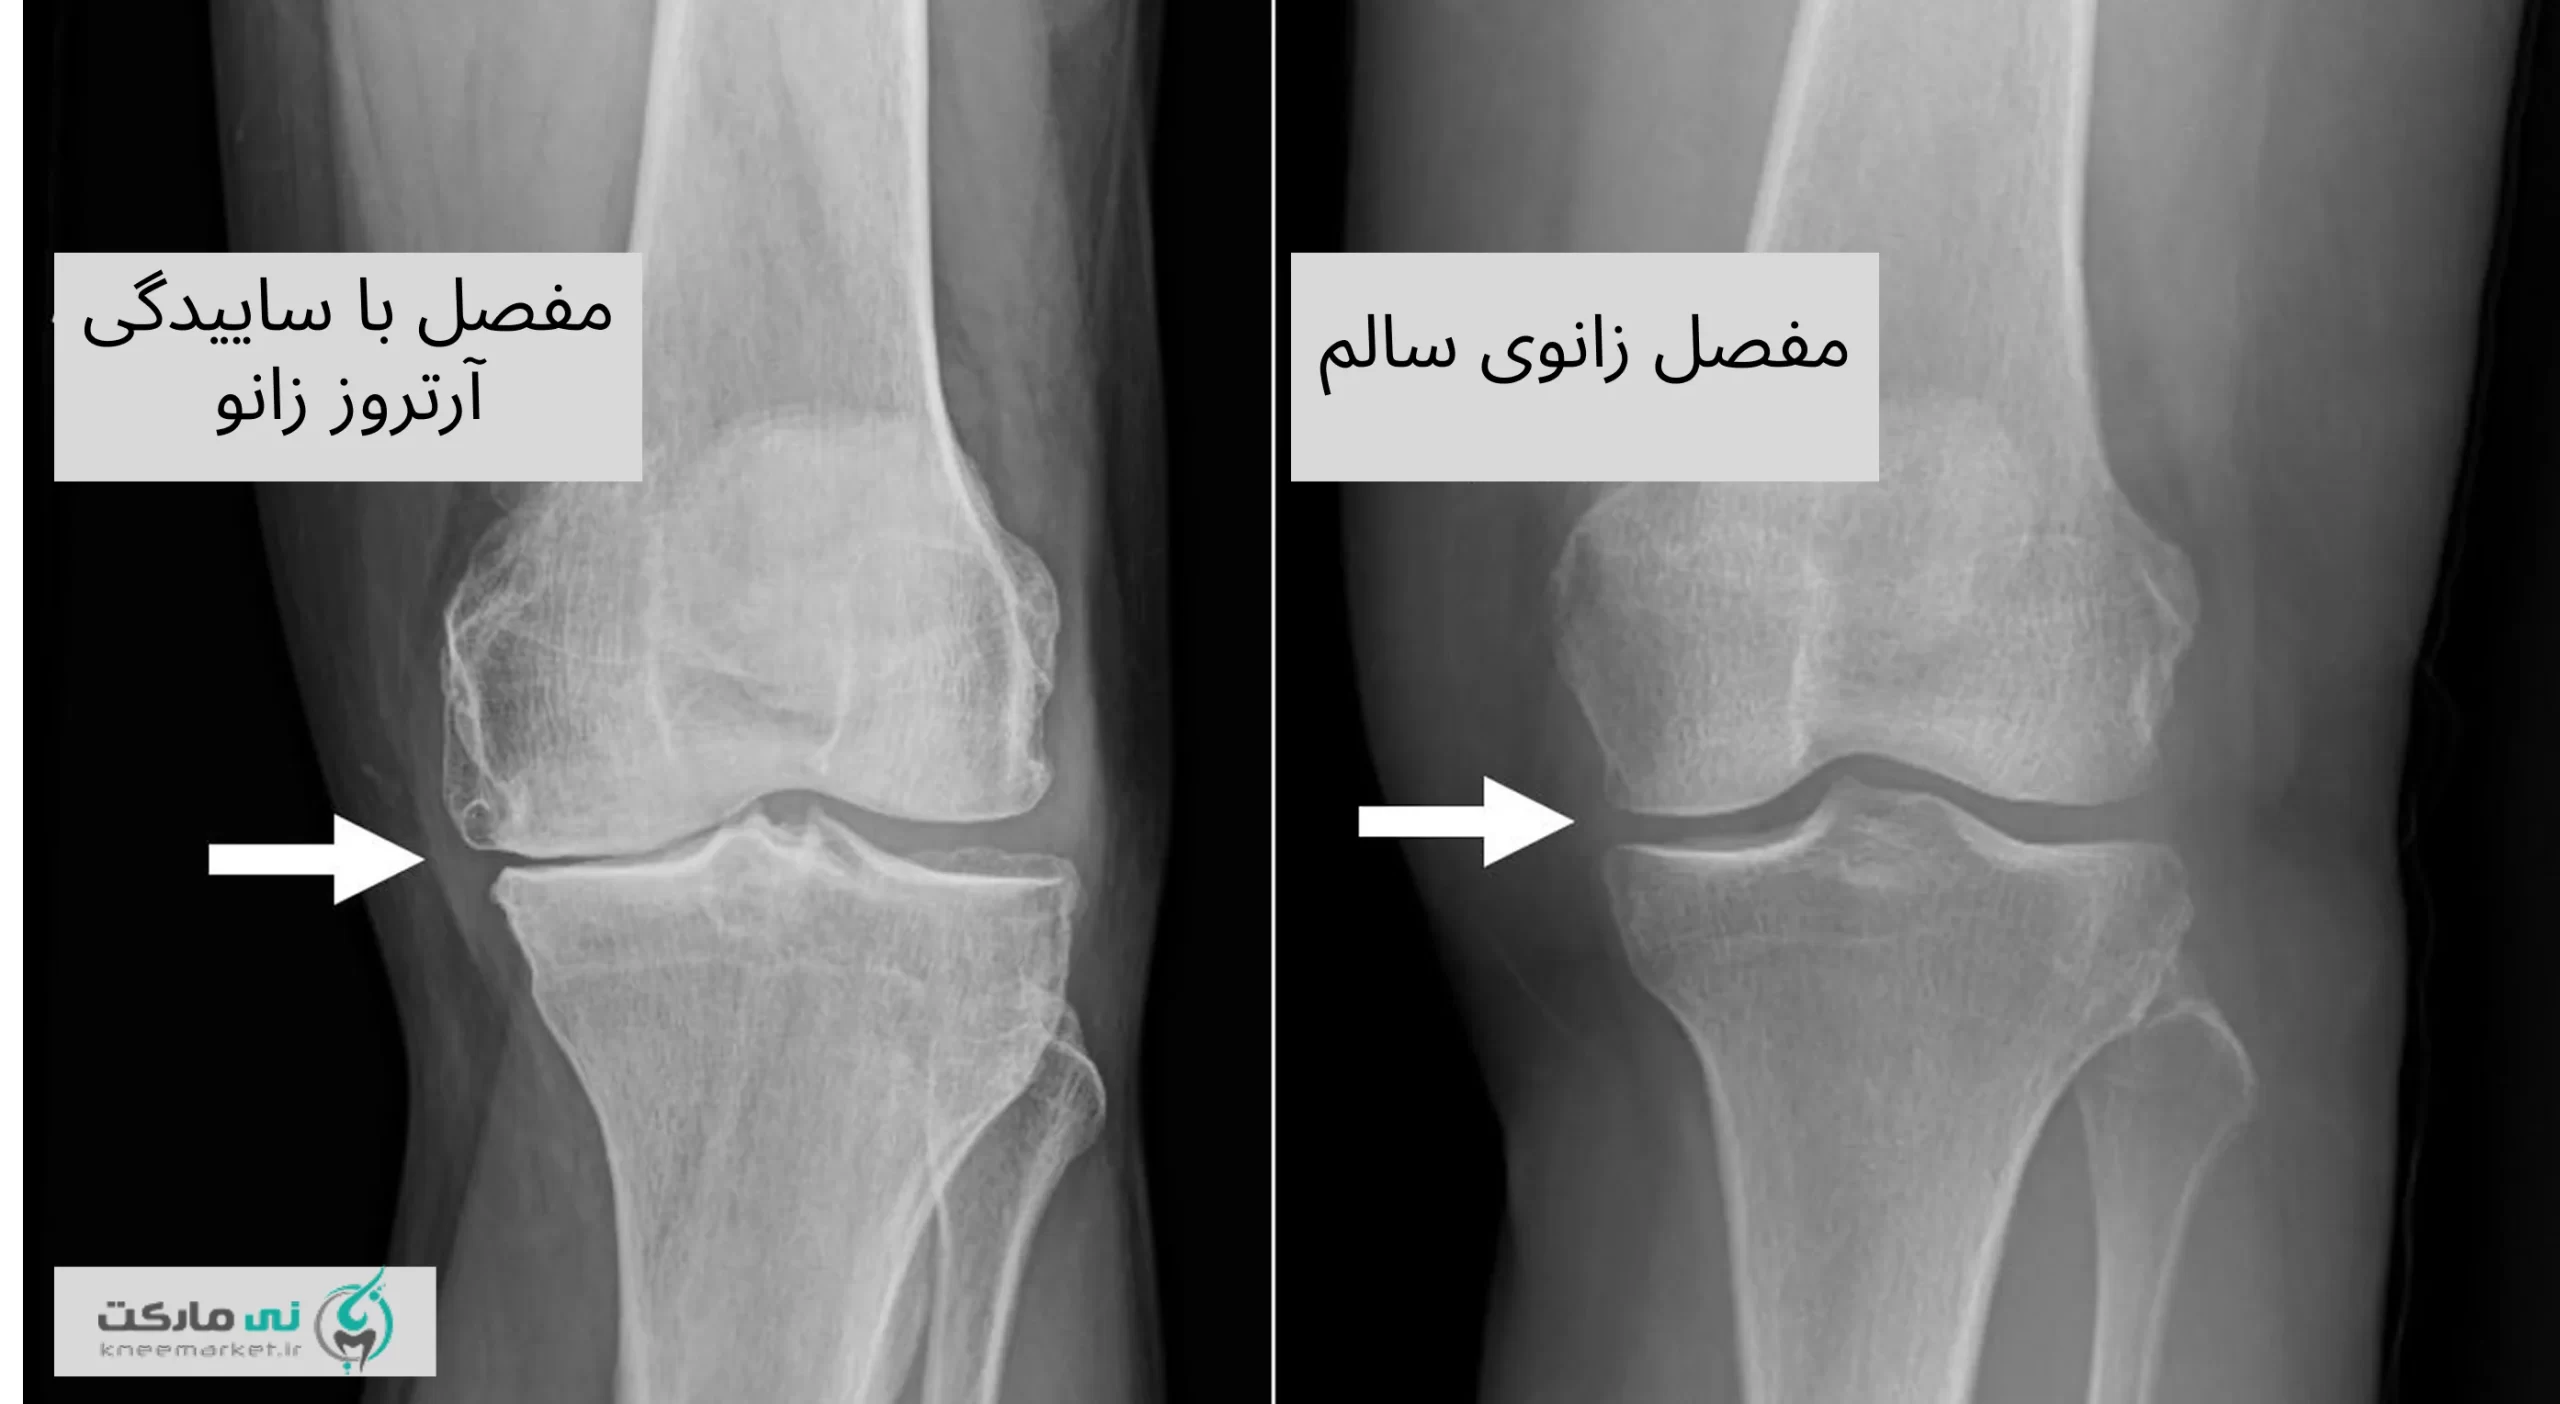

باید توجه داشت که آرتروز فقط مخصوص سنین بالا نیست. افرادی که دچار آسیبهای ورزشی، اضافهوزن، یا فعالیتهای سنگین و تکراری هستند، حتی در سنین جوانی هم ممکن است دچار آرتروز زانو شوند. تشخیص و کنترل زودهنگام میتواند از پیشرفت بیماری جلوگیری کند.

درمان آرتروز زانو بر اساس شدت

اما بهطورکلی درمان آرتروز زانو بر اساس شدت آسیب، درجه یا گرید، و علائم آن تعیین میشود.